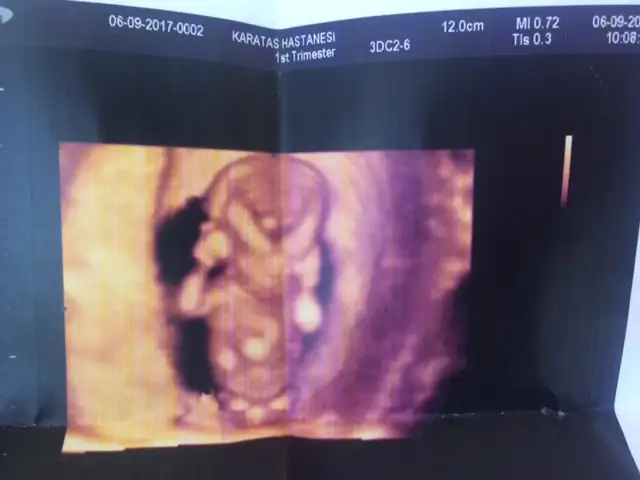

11 haftalıkken crl 48.33 mm cm olarakta 4,5 5 cm e yakın oluyor sanırım. Ultrason kağıdı verdiyse onda yazar. Başran popoya mesafesi crl diye bakabilirsiniz varsa.kızlar birşey soracağım. Benimle yakın tarihte olanlar ya da 11+6 da doktora gidenler beebklerinizin boyu kaç cm di? Bana 12 cm dedi. Fazla uzun geldi bana ama

onda da 12cm yazıyor yükleyeyim mi bir bakar mısın11 haftalıkken crl 48.33 mm cm olarakta 4,5 5 cm e yakın oluyor sanırım. Ultrason kağıdı verdiyse onda yazar. Başran popoya mesafesi crl diye bakabilirsiniz varsa.

Doğrudur o zaman :) uzun bir bebek olacak belki. Biraz da bebeğin pozisyonu önemli olan. Ayaklarını karnına doğru çekip yatarsa daha kısa görünür demişti doktor. Daha önce farklı çıkmıştı ultrasonda önemli değil demişti belki , sizinki uzattıysa ayaklarıonda da 12cm yazıyor yükleyeyim mi bir bakar mısın

Canım gönderdim resmini kuzunun. Yukarlarda azıcık =)Doğrudur o zaman :) uzun bir bebek olacak belki. Biraz da bebeğin pozisyonu önemli olan. Ayaklarını karnına doğru çekip yatarsa daha kısa görünür demişti doktor. Daha önce farklı çıkmıştı ultrasonda önemli değil demişti belki , sizinki uzattıysa ayaklarıbakalım bebeğine at fotosunu da . Diğer arkadaşlarda yardımcı olabilir.

Utanmış gibi poz vermişKızlar bakın benim kuzu bu. Ellerini almış kafasının arasına düşünüyor kara kara=)12 cm yazıyor burda. Doktor da öyle söyledi ama ben o an heyecandan soramadım birşey

İnanın bende anlamadım doktorun cinsiyeti nasıl tahmin ettiğini. Utandığından eminim çünkü direk poposunu döndü. Sonra doktor uğraşınca döndü ama bu sefer de yüzünü kapadı.Doktor %70 kız dedi. Hayırlısı bakalım.Utanmış gibi poz vermiş

Sizinkinin cinsiyeti belli mi acaba? O çıkıntı kızmı olduğunu gösteriyor erkek mi birtürlü çözemiyorum ben o işi